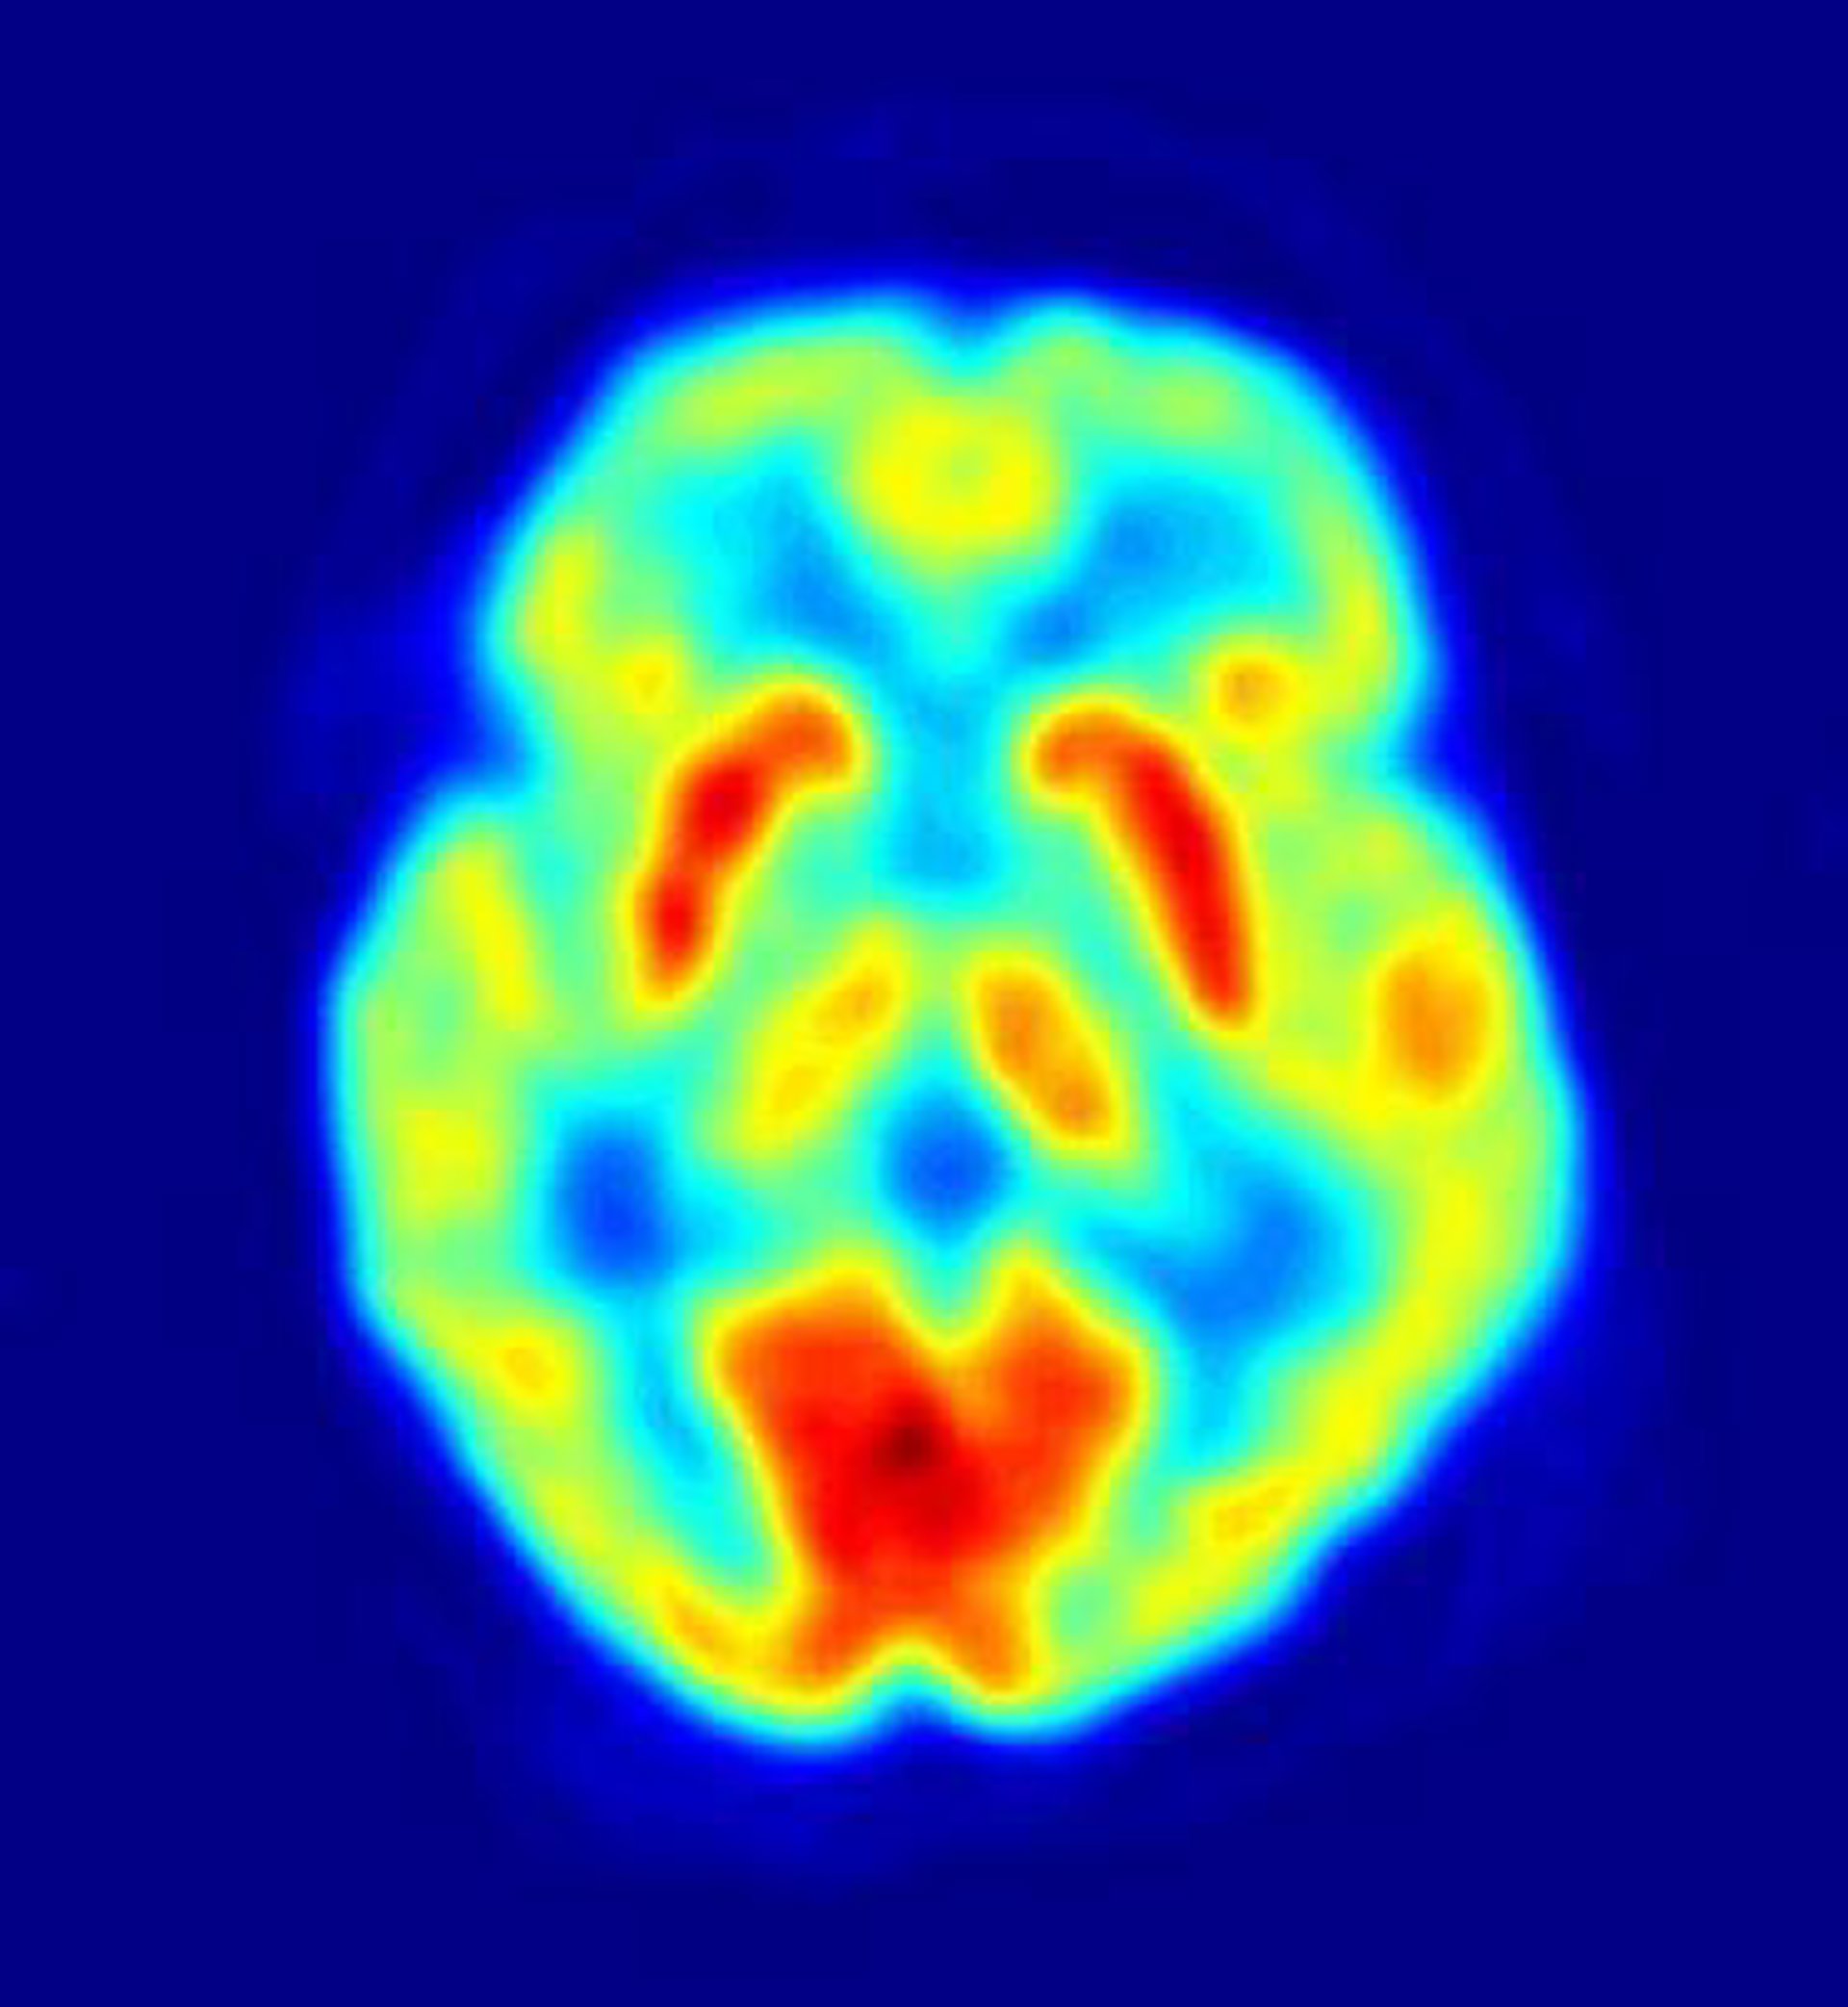

Los resultados de este trabajo demostraron que el incumplimiento de una promesa viene acompañado por un incremento de la actividad cerebral en areas del cerebro que juegan un papel importante en el proceso de la expresión de sentimientos y control de las emociones.

Este patrón de actividad cerebral sugiere que la ruptura de una promesa provoca un conflicto emocional en quien la incumple, debido a que el cerebro se ve obligado a no dar una respuesta honesta.

No obstante, el hallazgo más importante de este trabajo permite a los investigadores mostrar que los patrones cerebrales pueden predecir el comportamiento futuro de los individuos. De hecho, los sujetos que participaron en el experimento manteniendo la promesa y aquellos que las rompieron actúan exactamente igual cuando se realiza la promesa, ambos juran mantener su palabra. Sin embargo, la actividad cerebral en esta etapa delata a los incumplidores.